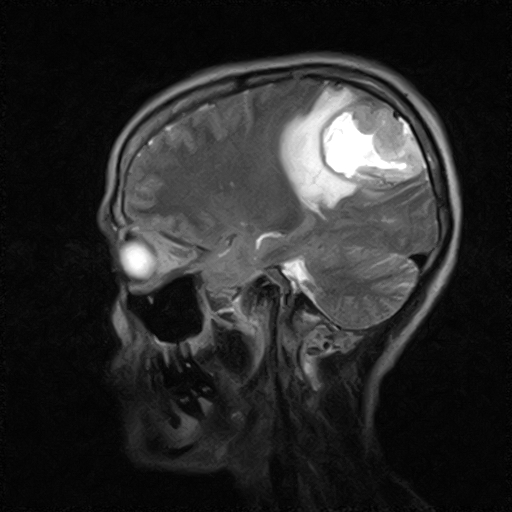

• Resonancia PATOLÓGICA DE CRANEO - MENINGIOMA -  SAG T1

• Resonancia PATOLÓGICA DE CRANEO - MENINGIOMA -  SAG T2